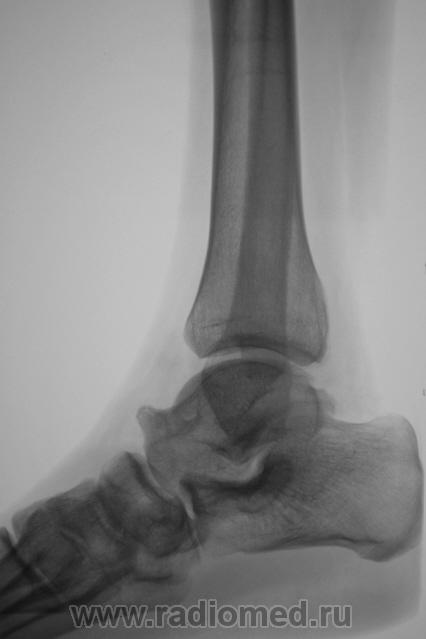

Пол пациента: Мужской пол Тип патологии: Другое Область исследования: Скелетно-мышечная система Методы исследования: Rg Пациент направлен врачом хирургом в рентгеновский кабинет по поводу болей в голеностопном суставе. Произведена рентгенография голеностопного сустава Ваше мнение уважаемые коллеги? Tue, 06/10/2009 - 22:21 #1 Ермолаев Offline Last seen: 8 years 11 months ago Joined: 07.02.2009 - 16:33 Posts: 670 Думаю, что имеет место артроз голеностопного сустава и таранно-ладьевидного, таранно-пяточного суставов. Только это следствие, а причина мне видится в наличии повреждения дистального межберцового синдесмоза. dok Tue, 06/10/2009 - 22:48 #2 В.Б. Серов Offline Last seen: 1 month 2 weeks ago Joined: 16.07.2008 - 10:15 Posts: 1361 Дугообразная деформация костей, с линейными зонами перестройки, плоскостопие. Полный комплект дефектов Зри в корень!

Думаю, что имеет место артроз голеностопного сустава и таранно-ладьевидного, таранно-пяточного суставов. Только это следствие, а причина мне видится в наличии повреждения дистального межберцового синдесмоза.

Дугообразная деформация костей, с линейными зонами перестройки, плоскостопие. Полный комплект дефектов